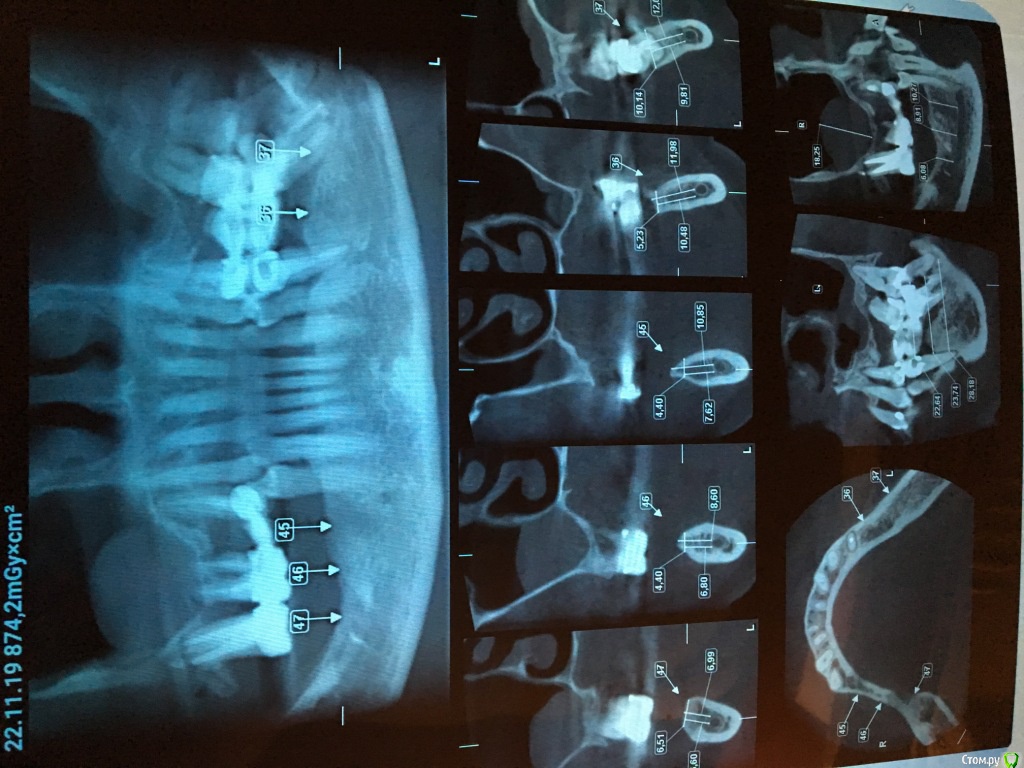

елена сок Опубликовано 29 ноября, 2019 Поделиться Опубликовано 29 ноября, 2019 Здравствуйте, уважаемые! НУЖЕН совет!!! У меня (увы!!!) жуткий пародонтит (виновата... как-то упустила...) Просто необходимо что-то с этим делать, но, к сожалению, бесконечные консультации со стамотологами в разных клиниках не привели к какому-либо решению., поскольку мнения, порой, кардинально разняться: от: 1. "оставить все как есть /пусть - и на время/,и следить и ухаживать за полостью рта крайне тщательно, 2. " все зубы под мостами удалить - и поставить импланты" , 3. " импланты противопаказаны!!!!- все зубы все-же удалить - и сделать бюгельные протезы"(вообще - жесть....) Голова кругом..... Проблема НЕ решается и я просто НЕ ЗНАЮ, что же мне делать. НЕТ вразумительного и объективного РЕАЛЬНО ВОЗМОЖНОГО в моей непростой ситуации решения. Прошу помощи! Ссылка на комментарий